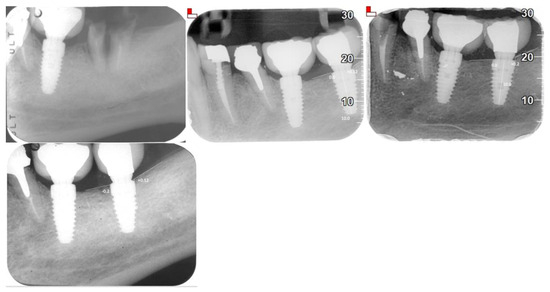

| Evaluation Methods | Orthopantomograms (OPG), cone beam computed tomography (CBCT), intraoral radiographs, clinical examinations |

| Implant Success Rate | 100% after 4 years |

| Peri-implant Bone Loss | Mean: 0.1208 mm (±0.1307) |

| Mesial Bone Loss | 0.14302 mm (±0.0107) |

| Distal Bone Loss | 0.09934 mm (±0.0143) |

| AVERAGE BONE LOSS | 0.1208 + −0.1307 |

| Mesial bone loss | 0.14302 + −0.0107 |

| Distal bone loss | 0.09934 + −0.0143 |